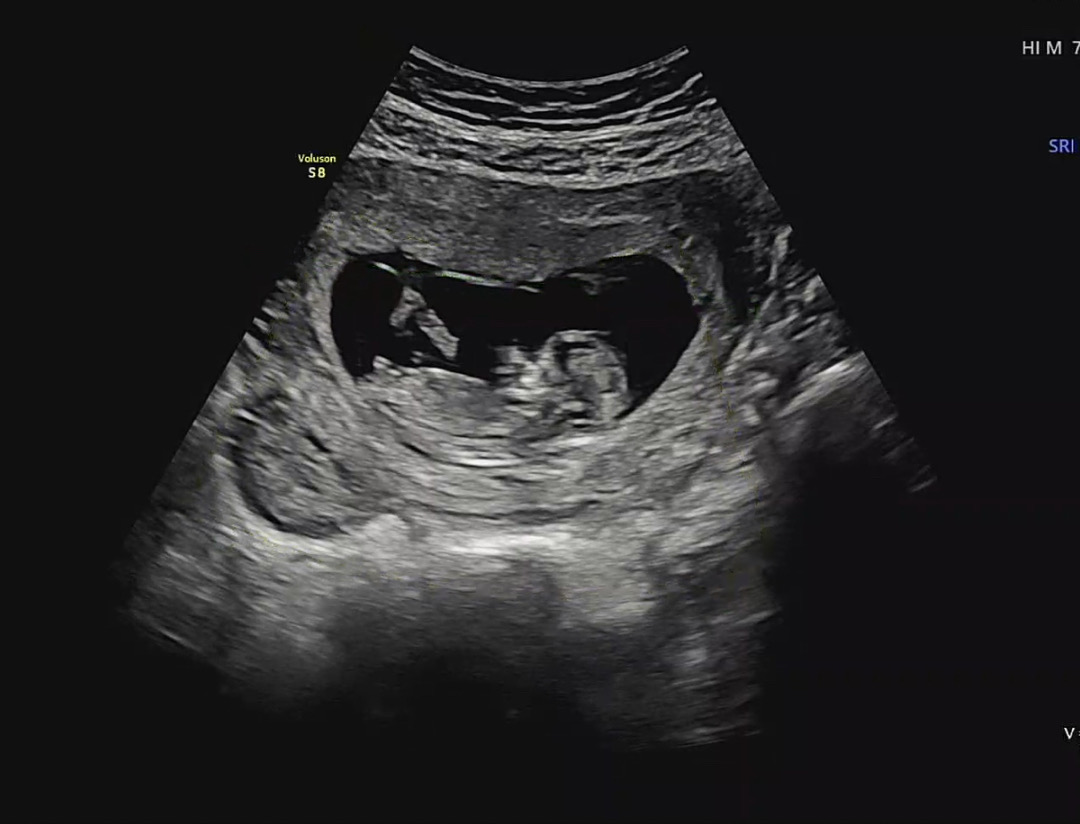

각도법 보실 줄 아시는분 계실까요?

다음주에 성별 들으러 가긴 하는데,, 너무 궁금해서요! 각도법 보실 줄 아시는분 계실까요??ㅎㅎ 전 백날 봐도 모르겠네요ㅋㅋㅋㅋ ㅠㅠ

흐릿해서 각도만봐서는 아들일꺼같네요